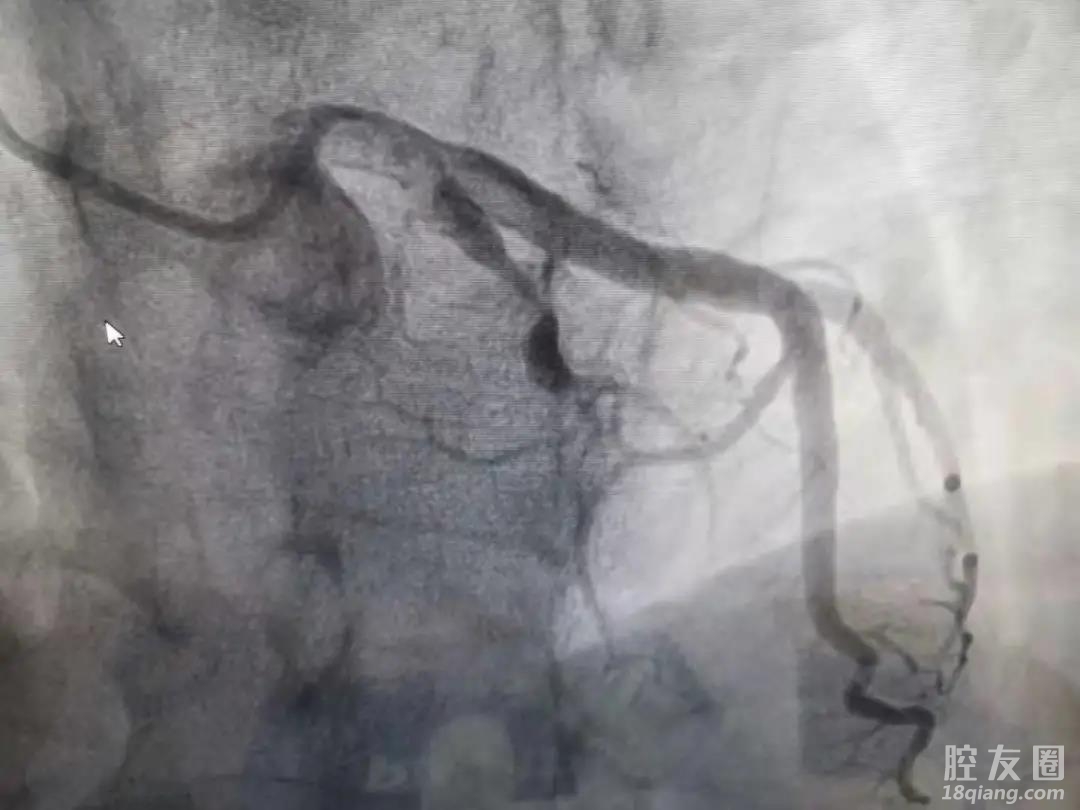

为进一步探明血管的拥堵程度,楼大叔又进行了心脏造影,发现前降支血管已经完全堵塞。

“现在我们都提倡精准治疗!”李宇琛主任说道,“在植入支架的过程中,我们采用了血管内超声。和传统的冠脉造影(冠脉造影:利用造影剂充盈管腔来显示血管情况)相比,血管内超声是可以直接进入到血管内部,通过超声查看血管里面的结构,可以更精准的判断病情、病变和植入支架的程度,用于指导治疗!”